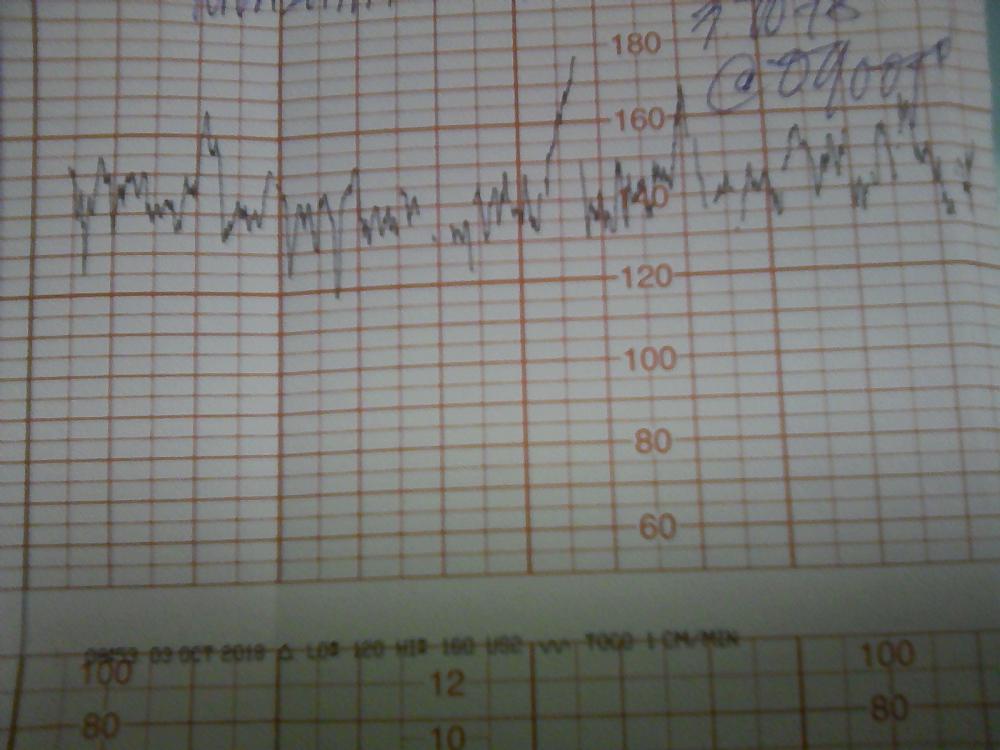

شوفو التخطيط فيه طلق أو لا والصور السوداء الباقي شنهي عنق الرحم أو الجنين مافهمت شيء لي ثلاث ايام بالتاسع وشكرا

شوفو التخطيط فيه طلق أو لا والصور السوداء الباقي شنهي عنق الرحم أو الجنين مافهمت شيء لي ثلاث ايام بالتاسع وشكرا

شوفو التخطيط فيه طلق أو لا والصور السوداء الباقي شنهي عنق الرحم أو الجنين مافهمت شيء لي ثلاث ايام بالتاسع وشكرا

شوفو التخطيط فيه طلق أو لا والصور السوداء الباقي شنهي عنق الرحم أو الجنين مافهمت شيء لي ثلاث ايام بالتاسع وشكرا